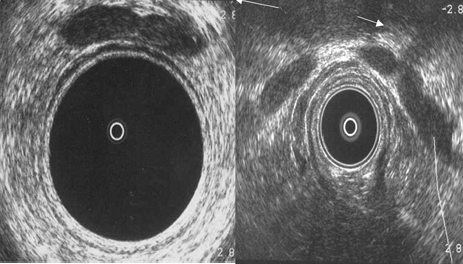

Ecografía rectal. Vesículas seminales